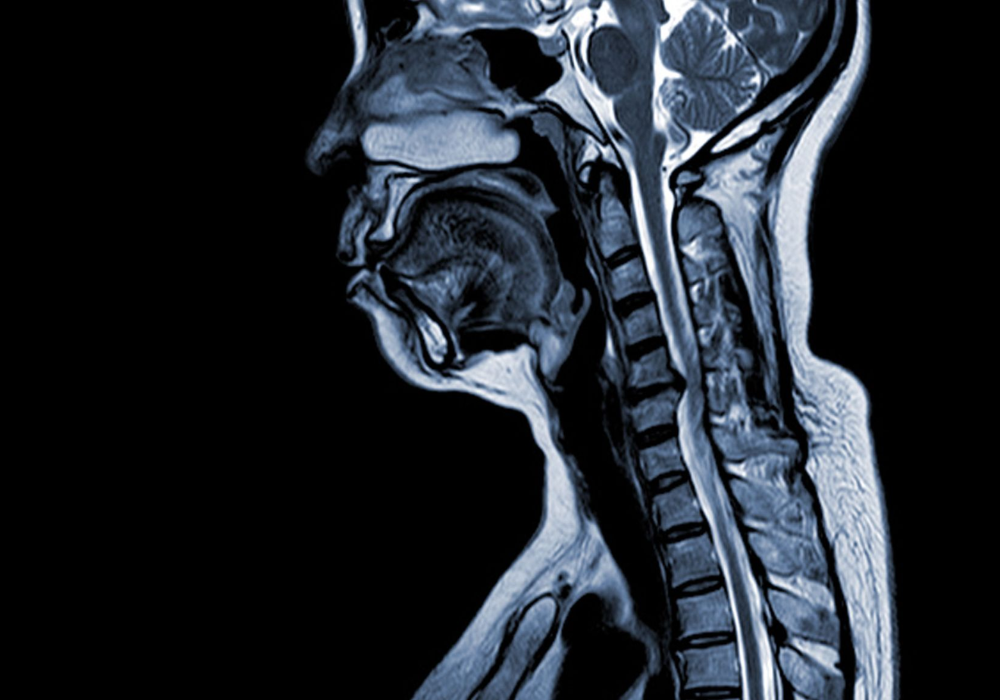

Radiology reading rooms are intentionally dim to optimise image contrast and reduce glare, supporting accurate interpretation. However, prolonged time in such settings coincides with reduce